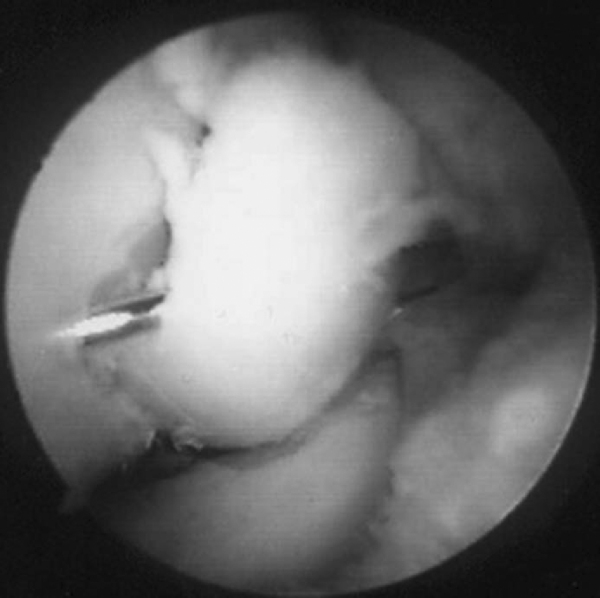

Once entrance into the joint is confirmed, the anterior aspect of the capitellum is evaluated. Loose bodies are removed through a proximal anterolateral portal. The proximal anterolateral portal is positioned 2 cm proximal and 1 to 2 cm anterior to the lateral epicondyle (

). This portal may be used as the initial portal in elbow arthroscopy. The blunt trocar is aimed toward the center of the joint while contact is maintained with the anterior humerus and pierces the brachioradialis muscle, brachialis muscle, and lateral joint capsule before entering the anterior compartment. The coronoid fossa is a common place for loose bodies to be localized (

Fig. 32-7

). Although the osteochondritic lesion may be noted on the anterior aspect of the capitellum (

Fig. 32-8

), it is most commonly noted on the posterior aspect and can be barely visualized with the scope in the anterior portal. One should always perform a varus and valgus stress test while the scope is in the anterior portal to document any concomitant instability of the elbow. Once a complete diagnostic arthroscopy of the anterior compartment of the elbow and removal of any associated loose bodies have been completed, the inflow is left in the proximal anteromedial portal and the scope is transferred to a straight posterior portal. The straight posterior or trans-triceps portal is located 3 cm proximal to the tip of the olecranon in the midline posteriorly [6] [16] (see

). The shaver is placed through the soft spot portal, and any loose fragments of the osteochondritic area are débrided. The necrotic bone is then removed, and in an attempt to stimulate blood flow, multiple drill holes are placed into the main body of the capitellum by use of either a drill or an awl (

Fig. 32-10

).

Figure 32-8 |